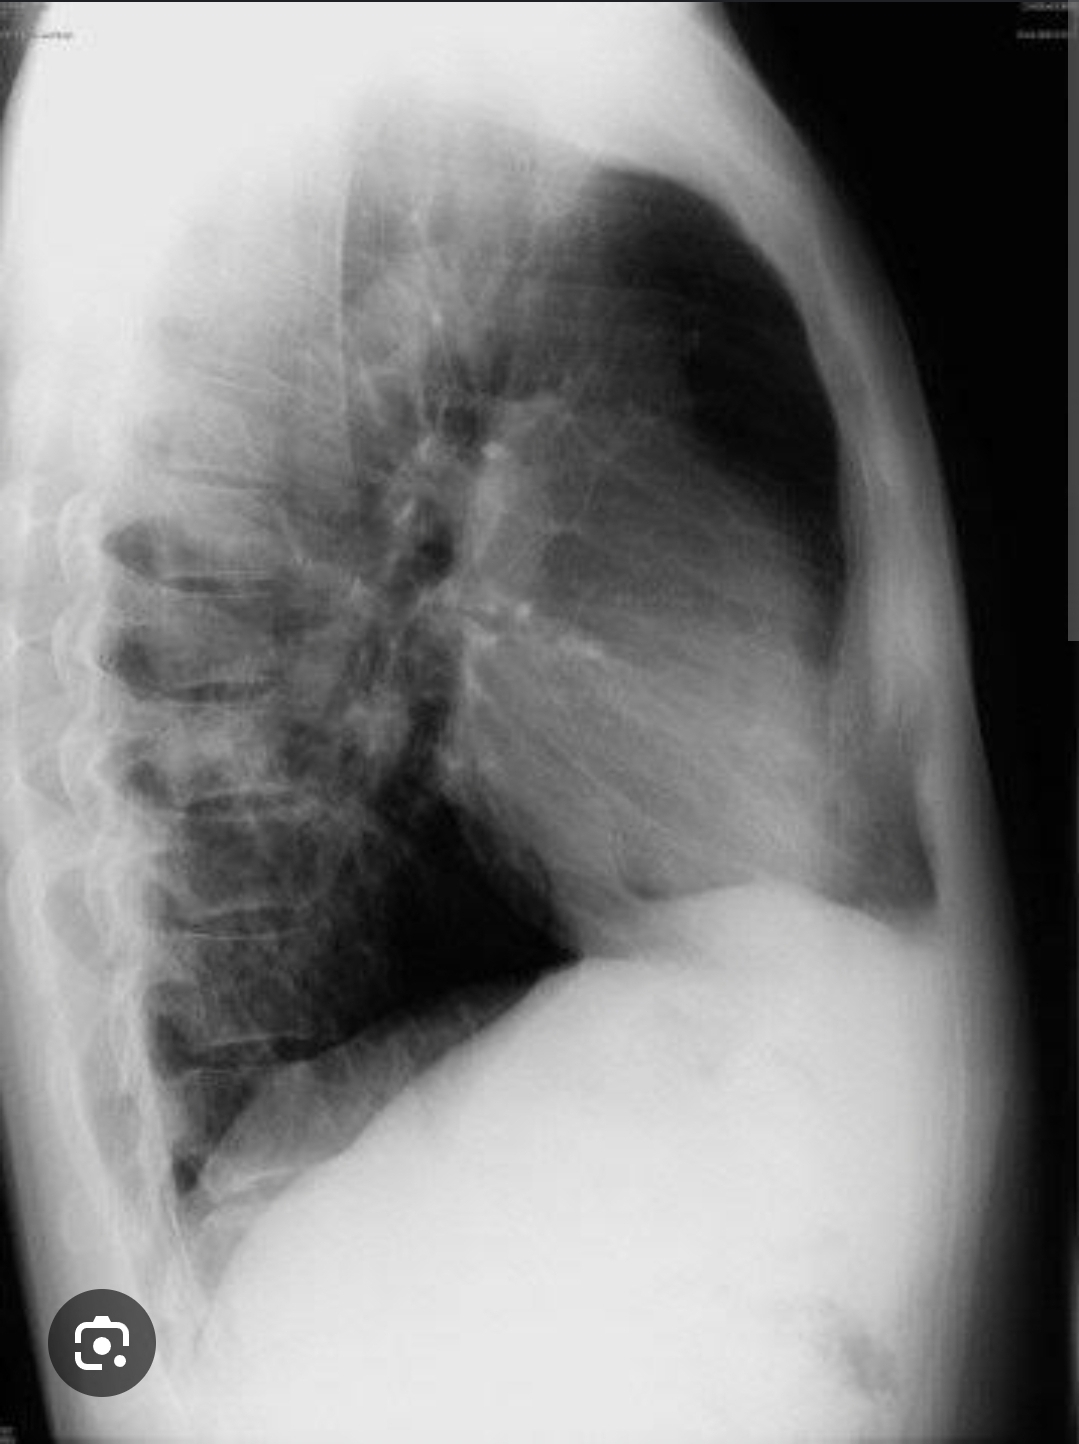

Sempre deve analisar rx em duas incidências , se possível PA e perfil esquerdo

Verdade, pois ganha noção de profundidade

Costofrenico lateral : encontro da pleura costal com a diafragmatica

Costofrenico posterior: encontri da pleura costal com a diafragmatica na parte posterior vista somente em perfil

Cardiofrenico: encontro da pleura diafragmatica com a mediastinal .